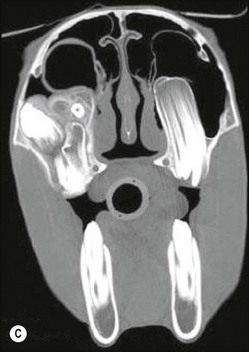

image image image

Fig. 13.43 Radiograph (A) and CT images (B and C) of a compound odontoma in a 2-year-old TB colt.

(Images courtesy of J. Easley.)